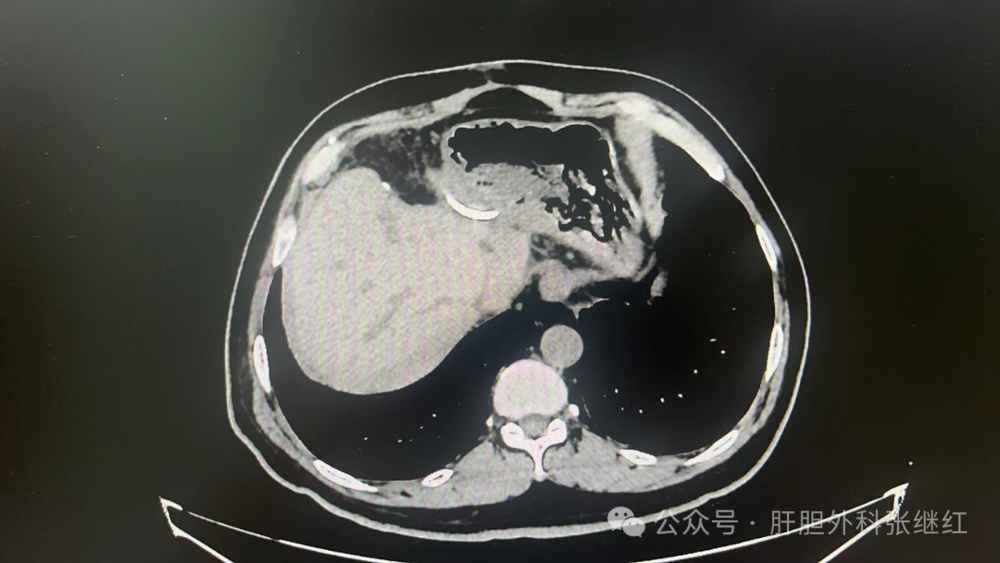

术后1月CT肝段面少许包裹积液

术后CT见包裹性积液消失